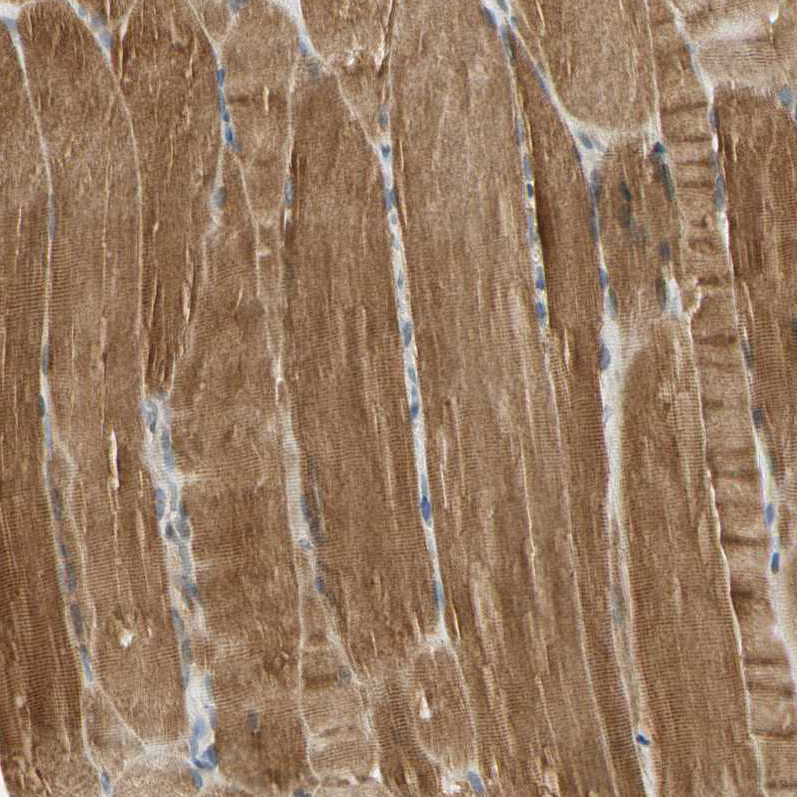

Immunohistochemical staining of human prostate shows moderate cytoplasmic positivity in glandular cells.